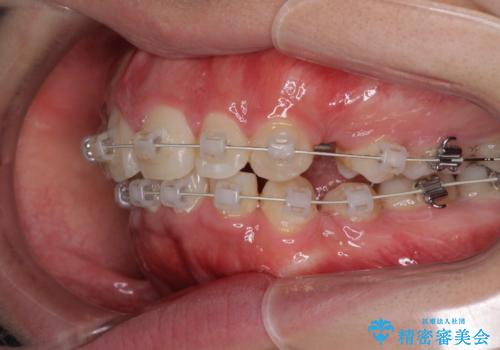

前から4番目の歯を抜歯することが多いのですが、右上の前から5番目の歯が神経の治療済みであり、こちらの歯を抜歯する計画としました。

通常より治療期間を要しましたが、健康な歯を残すことができました。